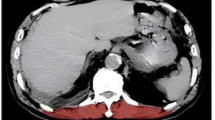

Pneumonia in elderly patients represent a critical clinical challenge with substantial mortality risks, where muscle deterioration has emerged as a potential prognostic biomarker. However, the specific morphological characteristics of the erector spinae muscle (ESM) in this vulnerable population and their predictive value for short-term outcomes remain poorly understood. This prospective observational cohort study enrolled 189 elderly patients (age 84.7 ± 4.1 years) diagnosed with pneumonia at Lishui Traditional Chinese Medicine Hospital. A pre-specified, retrospective analysis of baseline chest CT images was conducted to quantify erector spinae muscle (ESM) parameters, including cross-sectional area (ESMCSA), thickness (ESMT), fat infiltration rate (FI), and CT attenuation values. Clinical variables, inflammatory markers, and severity scores were prospectively collected. LASSO regression was applied for feature selection, followed by univariable and multivariable Cox proportional hazards analyses to determine factors associated with 90-day mortality. Among 48 non-survivors (25.4%), the death group exhibited significantly lower ESM CSA (adjusted for body surface area), ESMT, and albumin levels, alongside elevated FI, APACHE II/SOFA scores, CRP, and diabetes prevalence (all P < 0.05). Kaplan-Meier analysis revealed a 9.6-fold higher mortality risk (P < 0.001) in patients with lower ESMT/BSA. LASSO regression identified CRP, albumin, FI, ESMT, and diabetes as key predictors. Although univariable analysis associated lower ESMCSA/BSA, ESMT/BSA, and elevated FI with mortality (P < 0.05), multivariable Cox regression identified only higher albumin levels (HR = 0.882, 95% CI: 0.827–0.941) and ESMT/BSA (HR = 0.553, 95% CI: 0.449–0.683) as independent protective factors. Elevated CRP (HR = 1.098, 95% CI: 1.051–1.147) and FI (HR = 1.044, 95% CI: 1.006–1.084) independently predicted mortality. In patients with pneumonia, elevated CRP levels and the degree of erector spinae muscle fat infiltration were identified as independent risk factors for mortality, while higher albumin levels and the ratio of erector spinae muscle thickness to body surface area served as independent protective factors.